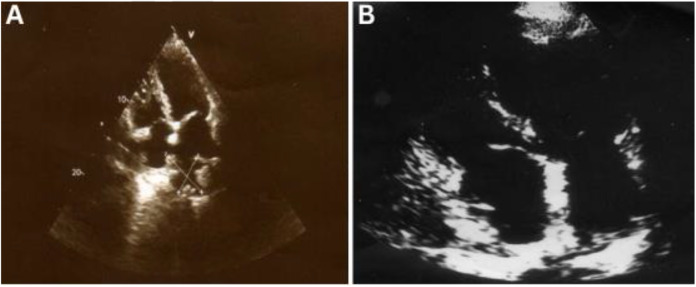

Endobronchial metastases extending to the heart from gastric cancer are rare. This case report describes a 69-year-old man who presented to a tertiary care hospital in Shahrekord, Iran, in 2022 with a history of cough and haemoptysis. He had previously undergone total gastrectomy and adjuvant chemotherapy for gastric adenocarcinoma three years earlier. Imaging and pathological evaluation confirmed endobronchial metastasis with extension to the left atrium. The patient responded well to chemoradiotherapy, maintaining a good quality of life.